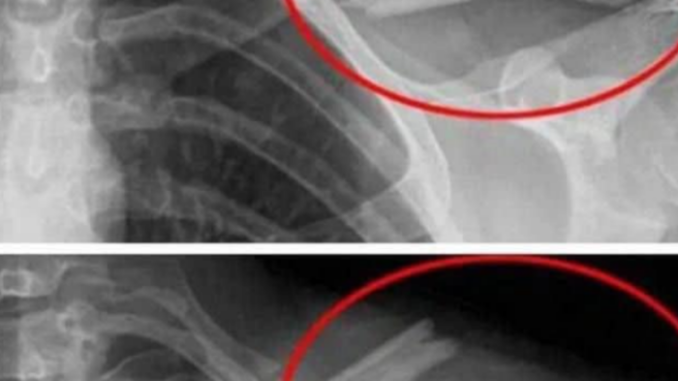

Pravidelná konzumace kolových nápojů může negativně ovlivnit zdraví kostí. Podle odborníka Richarda Piknera kolové nápoje brání vstřebávání vápníku v zažívacím traktu, což může zvýšit riziko onemocnění kostí, jako je osteoporóza.

Osteoporóza, často označovaná jako „tichá epidemie“, postihuje miliony lidí po celém světě.